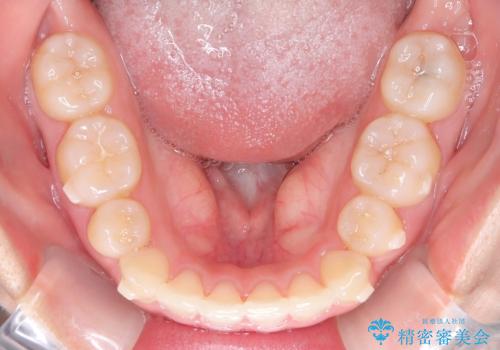

- 前歯のでこぼこが気になると来院されました。

奥歯の噛み合わせは綺麗に噛んでいたため、前歯の叢生(でこぼこ)を、短期間で治療完了するように計画しました。